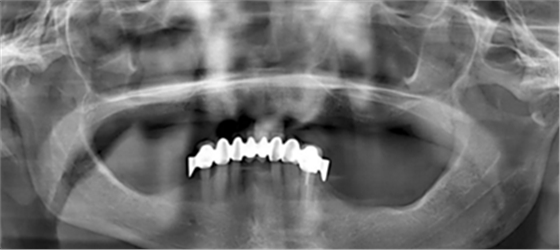

為了最大程度利用現(xiàn)有骨量,需要一個全程引導(dǎo)式的種植外科手術(shù)導(dǎo)板。在“以修復(fù)為導(dǎo)向”的方案設(shè)計過程中,根據(jù)CBCT數(shù)據(jù),對種植體與基臺中心軸向之間可能的最大夾角進(jìn)行計算。同時,計劃拔除 21 牙位之前未發(fā)現(xiàn)的殘根。該牙根之所以至今才檢測到,是因為曲面斷層片 (OPG) 上呈現(xiàn)出影像重疊(圖 1)。

(圖1)